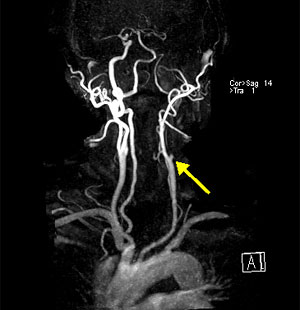

Артеріографія сонних артерій - з метою виявлення звужень, аневризм. Проводиться при виникненні транзиторних ішемічних атак, інсультів.

Найбільш частою причиною звуження або оклюзії сонної артерії є відкладення на внутрішніх стінках судини атеросклеротичних бляшок. Збільшення бляшки звужує артерію і уповільнює кровотік. На бляшках можуть утворюватися згустки крові (тромби) які ще більше перешкоджають кровотоку.

Частини тромбу або атеросклеротичної бляшки можуть відділятися і з током крові потрапляти в артерії головного мозку. В результаті чого відбувається так звана емболія судин головного мозку, що призводить до розвитку ішемічного інсульту.

Оклюзія сонної артерії може привести до розвитку інсульту або раптової швидкої смерті. Ризик для життя зростає при наявності ураження сонних артерій з обох сторін.